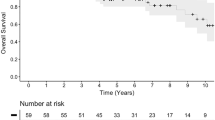

Retrospective imaging review of 46 patients from our hospital with brain tumors treated by PBT. The imaging findings were correlated with clinical and dose parameters.

Imaging changes were assessed by reviewing serial magnetic resonance imaging (MRI) scans following PBT over a follow-up period ranging from 1 month to 7 years. Imaging changes were observed in 23 patients undergoing PBT and categorized as pseudoprogression (10 patients, 43%), white matter changes (6 patients, 23%), parenchymal atrophy (6 patients, 23%), and cerebral large vessel arteriopathy (5 patients, 25%). Three patients had more than one type of imaging change. Clinical symptoms attributable to PBT were observed in 13 (28%) patients.

Two pediatric neuroradiologists conducted a consensus read of the pre-treatment and serial post-treatment imaging. The follow-up time period for imaging ranged from 1 to 87 months.

The effects of treatment with PBT have been of increasing interest for some time. Previous studies have looked at imaging changes in isolation in certain specific tumor groups and at certain individual clinical aspects. Most studies have also been limited by relatively short follow-up times, notable exceptions being a study by McGovern et al. looking at toxicities after PBT in patients with AT/RT, following up patients up to 53 months [10].

Our study had a much wider range of tumor types, as well as longer follow-up times, up to 87 months. As expected, the treatment histories were also more complex.

Our findings stress the need for continued close follow-up of pediatric patient populations treated by PBT to further document radiological and clinical changes, thus enabling us to assess the long-term effects and true benefits of this treatment method.